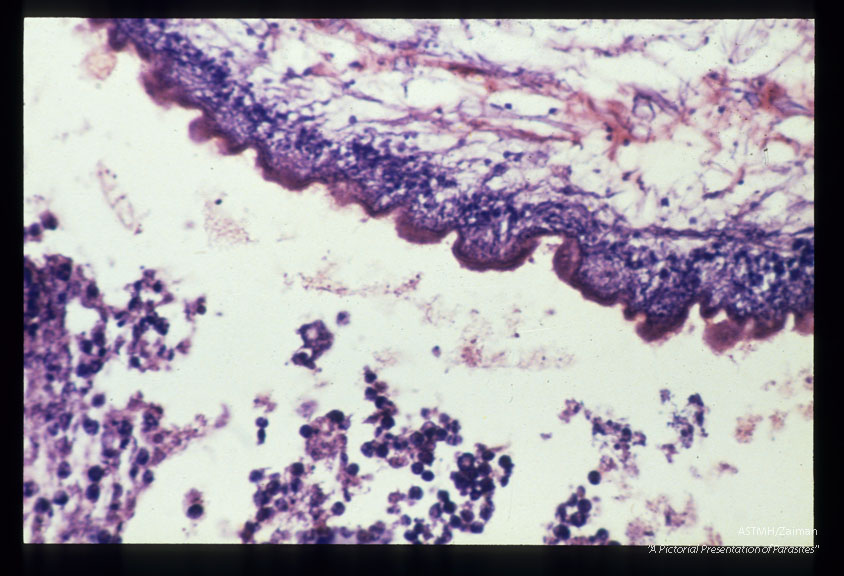

Multiple sections showing membranes, suckers and hooks.

Multiceps

Description: Multiple sections showing membranes, suckers and hooks.